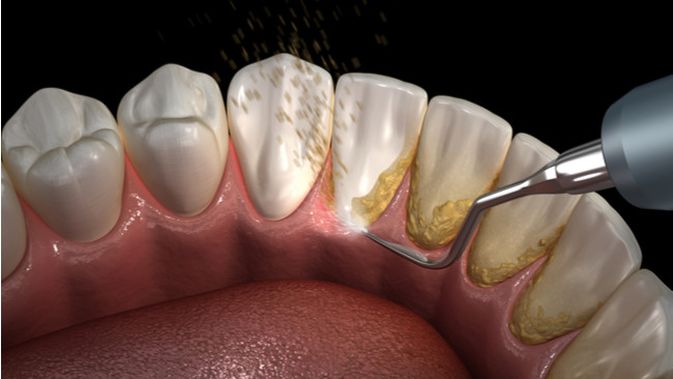

SCALING (Pembersihan Karang Gigi) - YouTube

SCALING (Pembersihan Karang Gigi) - YouTube